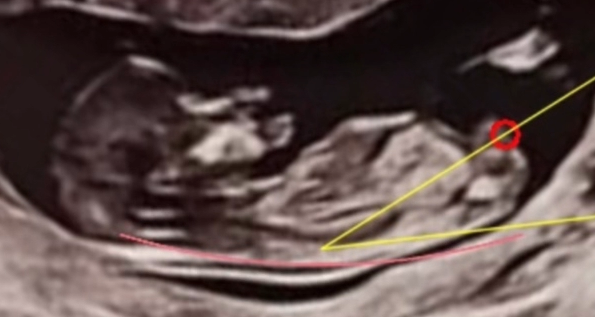

Understanding Nub Theory

Nub theory is based on the angle of the genital tubercle (or "nub") visible in ultrasound scans around 12 weeks. Research suggests that the angle of the nub can indicate the baby's gender.

- Angle pointing upward (≥30°): Likely a boy

- Angle parallel or downward (<30°): Likely a girl